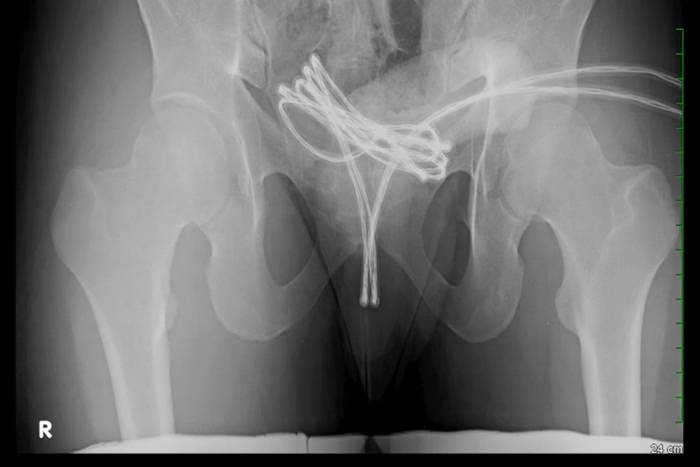

Médicos americanos descreveram, na edição de fevereiro da revista médica Cureus, o caso de um estudante universitário de 21 anos que inseriu um cabo USB na própria uretra para obter prazer s3xual. Ao perceber que o fio estava preso e que não conseguiria removê-lo por conta própria, o homem procurou ajuda médica em um hospital.

Os médicos descobriram que o cabo USB estava alojado na bexiga do jovem, dificultando a remoção. Foi necessário realizar um procedimento cirúrgico, sob anestesia geral, no qual se introduziu uma câmera na uretra, junto com o cabo. Com cuidado para evitar maiores danos, a equipe conseguiu remover o objeto.

Depois da retirada bem-sucedida, exames confirmaram que o universitário teve apenas ferimentos leves na uretra. Além de antibióticos e analgésicos, ele precisou usar cateter urinário por uma semana para facilitar a recuperação. Novos testes pós-procedimento confirmaram que o homem continuava se recuperando bem, sem danos permanentes.